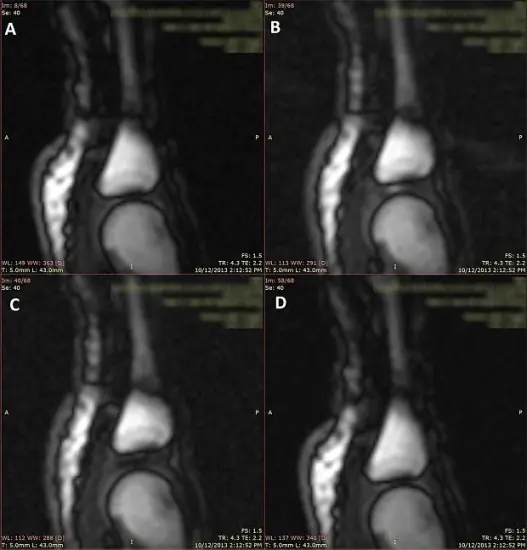

Las imágenes B y C: ¿Ven la burbuja?

Un reciente estudio proveniente de la Universidad de Alberta logra inclinar la balanza en favor de la cavitación al registrar bajo imágenes de resonancia magnética qué sucede cuando una persona se suena los nudillos, todo en un intervalo de 300 milisegundos. Pero lo más interesante es que el proceso podría ser benéfico, ya que ayudaría a mantener lubricada la articulación, que es lo que todos queremos. Esta idea va en contra del pensamiento general, aunque imagino que será suficiente para incrementar la cantidad de estudios. Ahora, la mayoría de las fuentes coinciden en un punto: Si el crujido está acompañado de dolor y sucede durante el movimiento normal de la articulación puede haber un problema, por lo que conviene consultar al médico.

El ruido de los nudillos generó durante décadas un amplio debate entre médicos e investigadores. La candidata número uno es la cavitación. Ante la leve separación de la articulación, la cápsula sinovial que la envuelve aumenta su volumen. Esto causa un entorno de baja presión, y provoca que los gases en el líquido sinovial (dióxido de carbono, nitrógeno y oxígeno) se separen del fluido, formando una burbuja. El origen del ruido es la formación de la cavidad y la burbuja, no su colapso. Los gases necesitan entre 10 y 30 minutos para ser reabsorbidos por el líquido sinovial, y por ese motivo es que sonarse los nudillos no es algo que se pueda hacer constantemente (hay excepciones, claro).